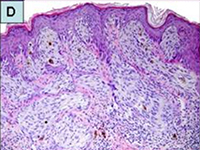

女児、14歳。新たに出現した腫瘍の評価のため受診した。身体診察では8mm大の淡紅色~褐色のまだら状の外観を呈する結節性病変(papulonodule)が認められ、生検を行った。病理診断報告書には病理標本の代表的な部分が示されており、…